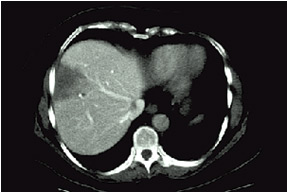

CT vyšetření břicha: Jedná se o speciální vyšetření pomocí rentgenových paprsků, cílených na zkoumanou oblast, jejíž obraz je převáděn do počítačové podoby. Podává nám podrobné informace o vyšetřovaných orgánech, velikosti nádorových ložisek, jejich vztahu k jiným strukturám. Před vyšetřením či během něj se podává také kontrastní látka a to ve formě roztoku, který se popíjí nebo se kontrastní látka podává do žíly.

Obrázek 4: Játra v CT obraze, tmavší oválné ložisko vlevo je nádor.